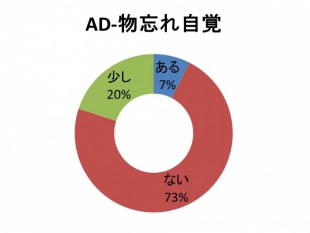

Q 認知症の人は認知症であることを自分で自覚していますか?

外来で認知症の診断をする場合、軽い認知症の人に「認知症であると診断すること」は難しいことが多いです。ご家族から話を聞いて認知症であるとわかることもよくあります。

その理由として患者さん自身が物忘れを自覚していないことが多く、当院で調べた結果では73%の方がご本人に物忘れの自覚が全くないようでした。20%の方は少し物忘れの自覚があるとのことですが、よく聞くと実際は自分ではあまり思っていないものの周りから物忘れを指摘されるためのようです。